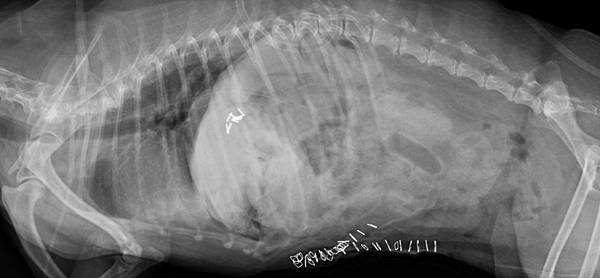

安咕來檢查的時候發現有肝腫瘤+膽囊黏液囊腫

可以看到腫瘤非常龐大

手術後X光